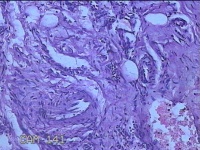

右手掌肿物

性别

女

年龄

32岁

临床诊断

1.右手掌肿物性质待查?右腕管综合征

一般病史

发现右手掌肿物疼痛伴拇示中指感觉迟钝约6年。

标本名称

大体所见

灰白粉红色肿物2.5x2x0.8cm一个,表面光滑,切开肿物呈实性,切面灰白粉红色,质软。